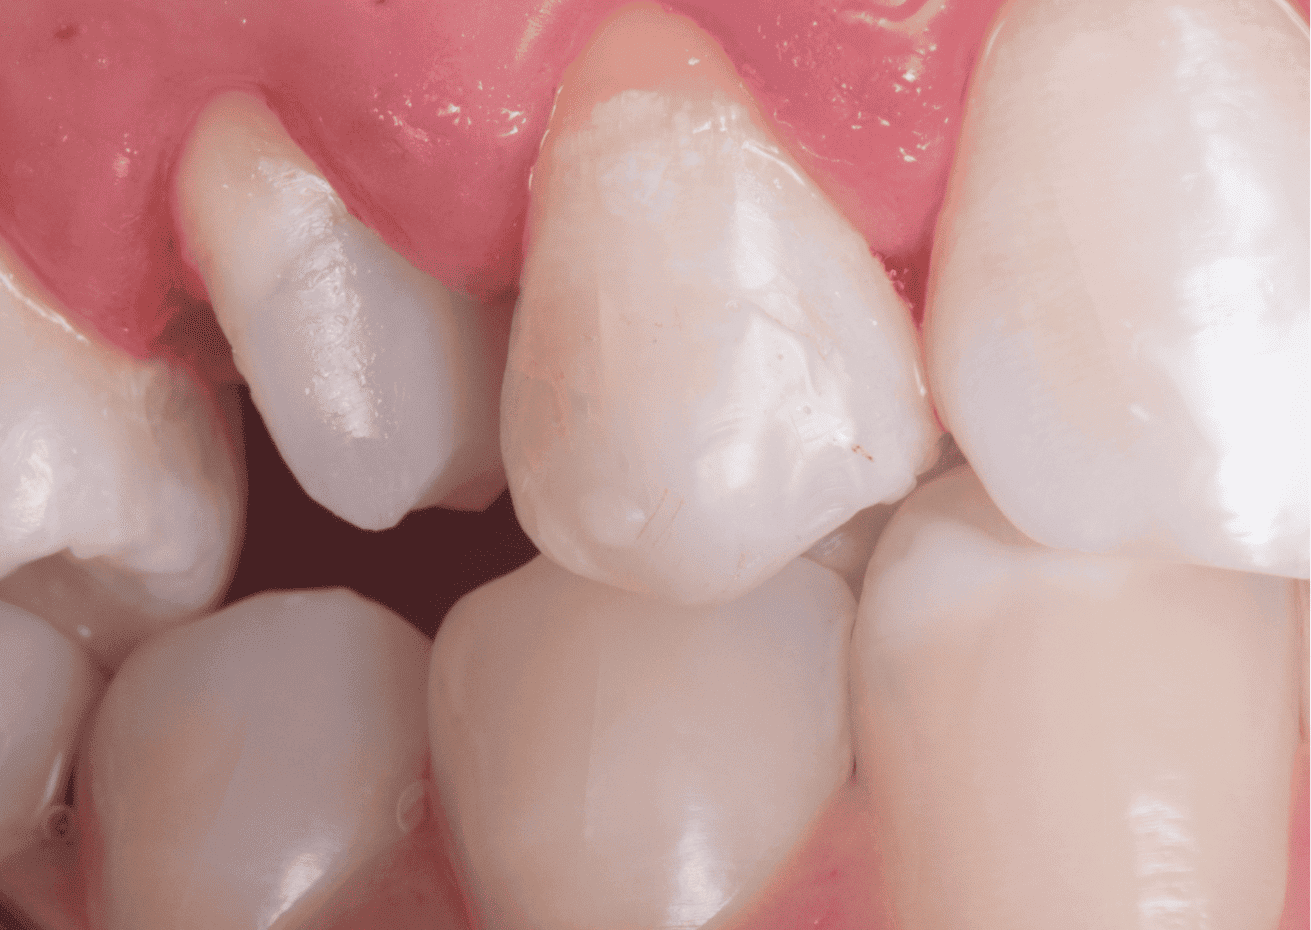

Paciente apresentou-se com elemento 15 com a necessidade de reabilitação protética devido a extensa perda de estrutura dentária.

O exame clínico inicial, do dente 15, apresentava selamento provisório com ionômero de vidro e exame radiográfico apresentava alívio de 2/3 do conduto.